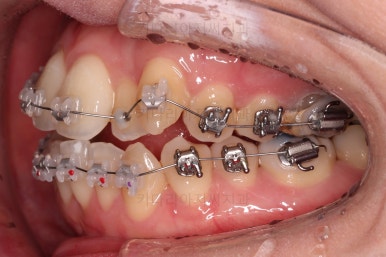

초진 시, 입안의 모습입니다.

좌측 송곳니가 덧니처럼 튀어나가 있고, 송곳니 옆의 작은 억므니가 안으로 쏙 들어가서 덧니 느낌이 더 강조되어 보이네요.

위아래 앞니가 긴밀하게 겹침이 없는 약간의 개방교합(오픈바이트, Openbite) 경향이 보입니다.

이번에 선택하신 장치는 자가결찰 세라믹 중에 엠파워 클리어라는 장치인데요.

흔히들 아시는 클리피씨도 같은 분류의 장치입니다.

철사가 들어가니 삐뚤한 치열이 더 강조되어 보이네요.